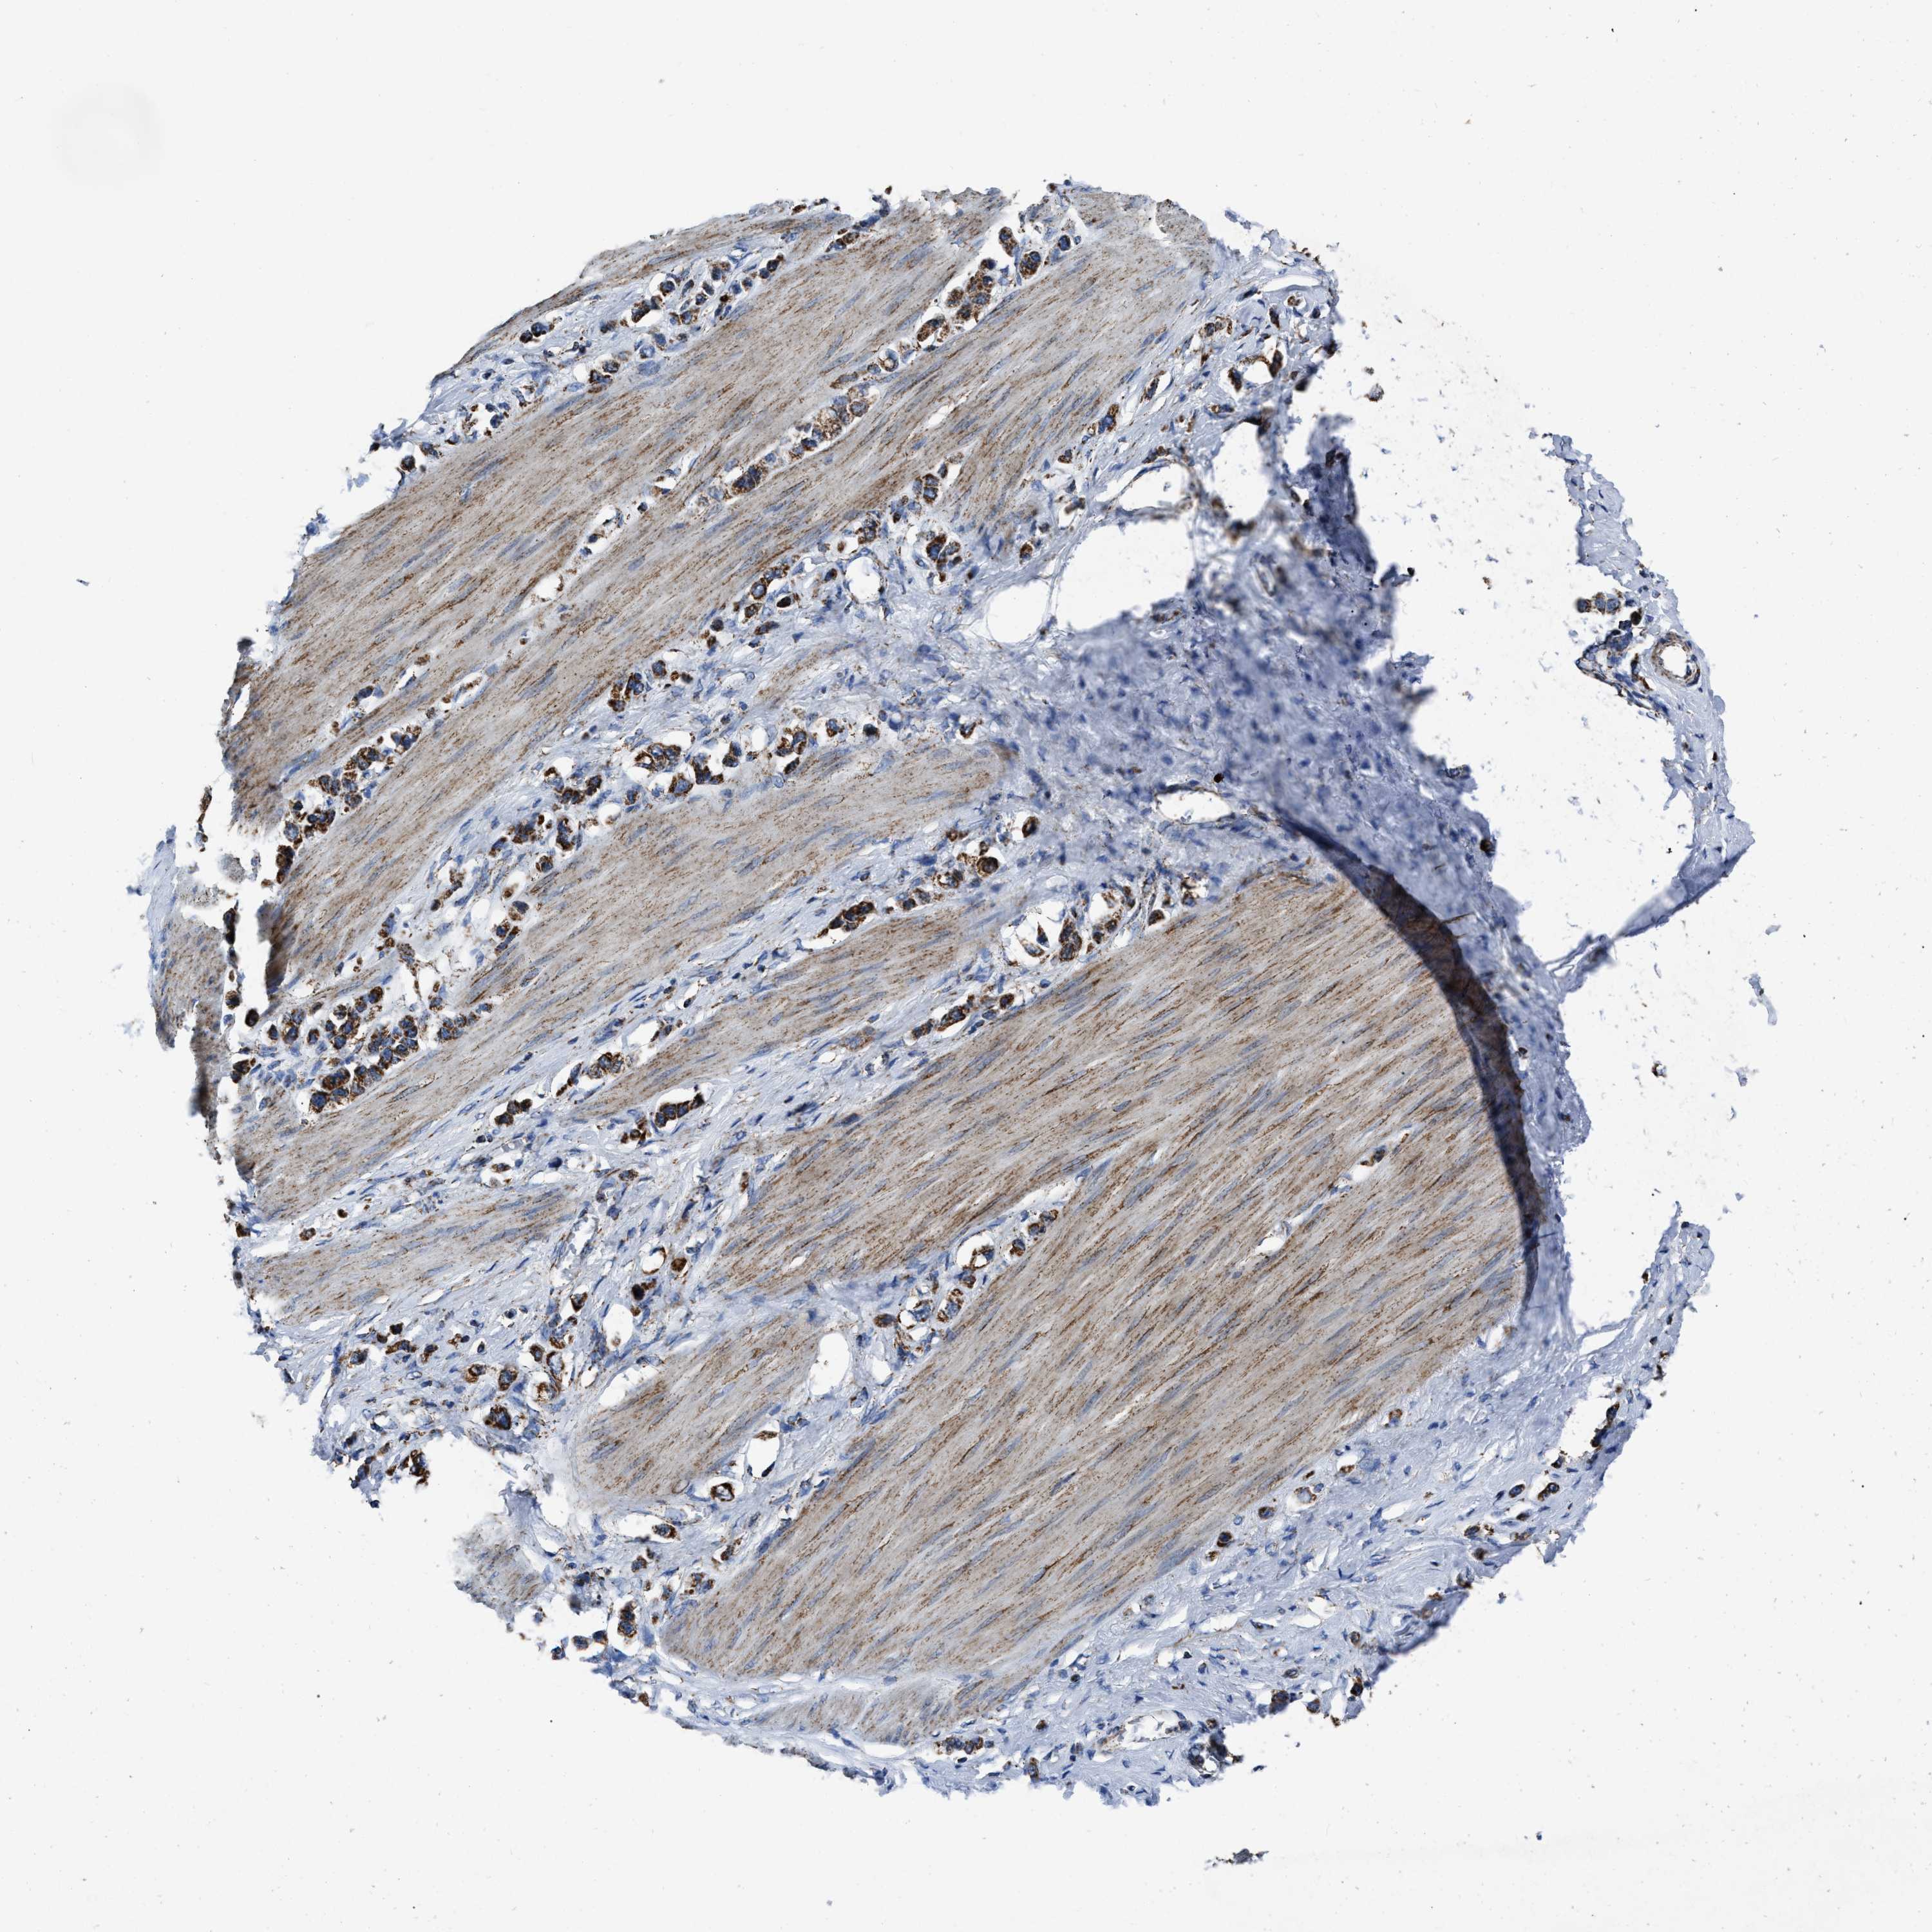

STOMACH CANCER - Protein expressioni

A mouse-over function shows sample information and annotation data. Click on an image to view it in a full screen mode. Samples can be filtered based on level of antibody staining by selecting one or several of the following categories: high, medium, low and not detected. The assay and annotation is described here.

Note that samples used for immunohistochemistry by the Human Protein Atlas do not correspond to samples in the TCGA dataset.

Antibody stainingi

Antibody staining in the annotated cell types in the current human tissue is reported as not detected, low, medium, or high, based on conventional immunohistochemistry profiling in selected tissues. This score is based on the combination of the staining intensity and fraction of stained cells.

Each image is clickable and will lead to virtual microscopy that enables deeper exploration of all samples and also displays staining intensity scores, fraction scores and subcellular localization as well as patient and tissue information for each sample.

Antibody HPA018893

Staining

High

Medium

Low

Not detected

Intensity

Strong

Moderate

Weak

Negative

Quantity

>75%

75%-25%

<25%

None

Location

Nuclear

Cytoplasmic/membranous

Cytoplasmic/membranous,nuclear

Adenocarcinoma, NOS